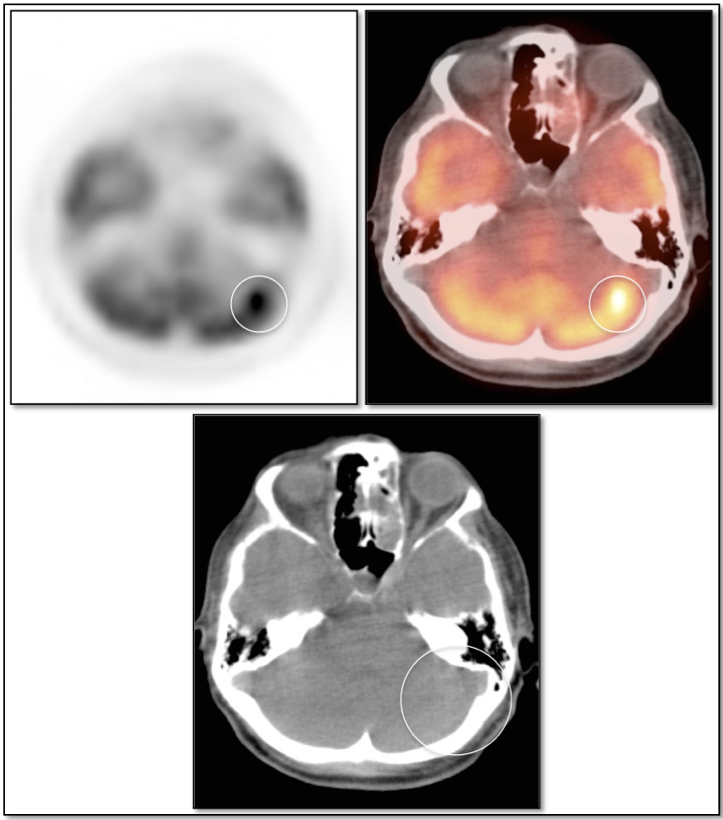

- Differentiate radiation necrosis (or chemonecrosis) from active malignancy.

Radiation Necrosis (or Chemonecrosis):

- Necrosis presents months to years after radiation therapy (rarely < 3 months post radiation).

- Difficult to differentiate necrosis from malignancy on MRI, as both demonstrate enhancement.

- Necrosis is typically non-avid on PET images.

- Recurrent malignancy will demonstrate FDG uptake, often focal and involving only a small portion of a surgical cavity. The uptake may be intense (an easy diagnosis) or may be minimally above adjacent background uptake (a more difficult diagnosis, which may require follow-up).

- FDG-avid recurrence should correspond to the area of enhancement noted on MRI (MRI should be done first, with images available at time of PET/CT interpretation).

- If no evidence of pathologic uptake, we report, “There is no evidence of high-grade tumor recurrence.”

Crossed Cerebellar Diaschisis:

- May see generalized decreased FDG uptake in the cerebellar hemisphere opposite of a supratentorial abnormality (e.g. tumor, edema, infarct, gliosis).